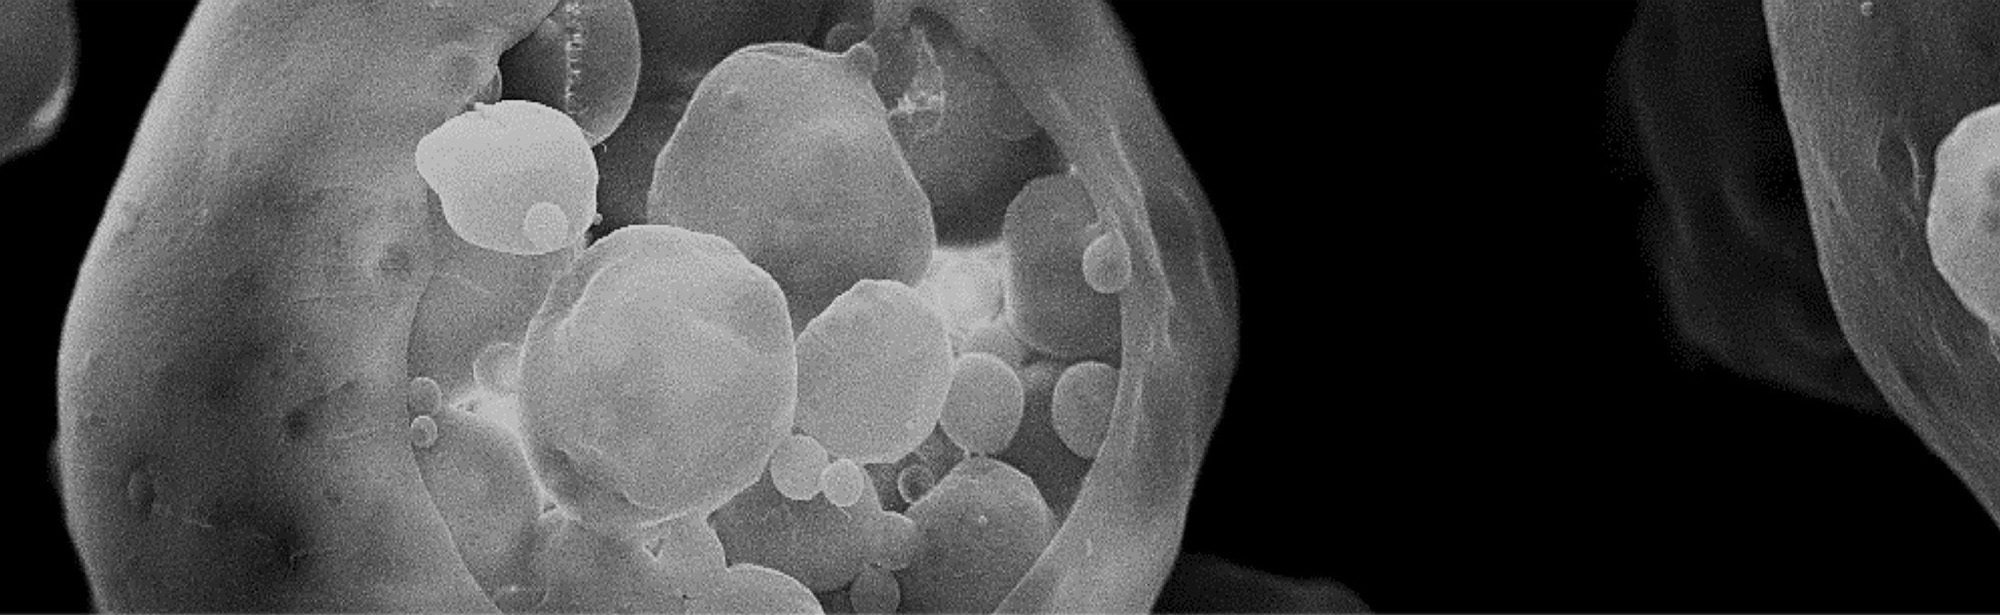

scanning electron microscope of outer membrane vesicles used for drug delivery

At Cornell, biomedical engineering faculty and students use engineering to control how and when medicines are delivered. They study these medicines’ effects on cells and tissues, and their efficacy in trials. Their projects aim to precisely target medicines, such as cancer treatments. They also develop devices for long-lasting injections and systems for vaccine delivery or single-cell genome sequencing or to understand the impact of outside influences on cells. The work integrates investigators working across length scales in all fields of engineering and also include investigators in chemistry, cell biology, genetics, immunology, veterinary medicine and human medicine.